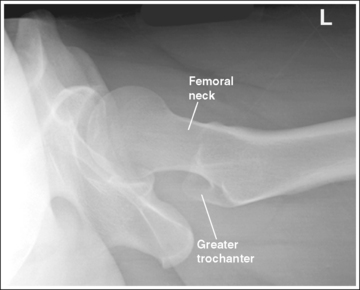

The femoral neck is demonstrated without foreshortening. The proximal aspects of the greater and lesser trochanters are demonstrated at approximately the same transverse level.

• An axiolateral projection of the hip is obtained by placing the patient on the imaging table in an AP projection, with the unaffected hip positioned next to the lateral edge of the table. Flex the patient's unaffected leg until the femur is as close to a vertical position as the patient can tolerate, and then abduct the leg as far as the patient will allow. Support this leg position by using a specially designed leg holder or suitable support. Flexion and abduction of the unaffected leg move its bony and soft tissue structures away from the affected hip. Inadequate flexion or abduction of the unaffected leg results in superimposition of soft tissue onto the affected hip, preventing visualization of the affected hip (see Image 12).

The lesser trochanter is in profile posteriorly, and the greater trochanter is superimposed by the femoral shaft.

• Rotation of the patient's affected leg determines the relationship of the lesser and greater trochanter to the proximal femur on an axiolateral hip projection. In general, when a patient is placed on the imaging table and the affected leg is allowed to rotate freely, it is laterally (externally) rotated.

• Effect of leg rotation on proximal femur visualization. To position the proximal femur in a lateral projection (90 degrees from the AP projection), demonstrating the lesser trochanter in profile posteriorly and superimposing the greater trochanter by the femoral shaft, the affected leg must be internally rotated until an imaginary line drawn between the femoral epicondyles is positioned parallel with the imaging table. The patient's foot is angled internally 15 to 20 degrees from a vertical position (Figure 7-18). If the affected leg is not rotated internally, the greater trochanter is demonstrated posteriorly and the lesser trochanter is superimposed over the femoral shaft (see Image 14). How much greater trochanter is demonstrated without femoral shaft superimposition depends on the degree of external rotation. Greater external rotation increases the amount of greater trochanter shown.

IMAGE 14

• Positioning for a proximal femoral fracture or dislocation. When a patient has a dislocated hip or a suspected or known proximal femoral fracture, the leg should not be internally rotated, but left as is. Forced internal rotation of a dislocated hip or fractured proximal femur may injure the blood supply and nerves that surround the injured area. Because the patient's leg is not internally rotated in such cases, it is acceptable for the greater trochanter to be demonstrated posteriorly and the lesser trochanter to be superimposed over the femoral shaft (see Image 15).